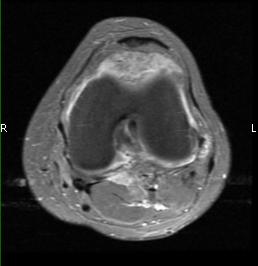

MRI (Fig. 1-10)

- Periarticular or synovial nodular mass with varying degrees of bone erosion.

- Nodular lesion with areas of hemosiderin (low signal on all sequences) and hemorrhage.

- On fat suppress images the tumor is high signal and hemosiderine cannot be seen.

- Joint effusions and bony erosions are well demonstrated. As with CT, contrast enhancement is typical.

Fig. 1-10: Magnetic Resonance of a PVNS of the knee shows a synovial mass with minimal bone erosion of the medial articular plate. On T1W and T2W images shows a tumor with low intensity areas (hemosiderin) and hemorrhage. Joint effusion is well demonstrated. Post contrast images demonstrate an irregular pattern of enhancement.